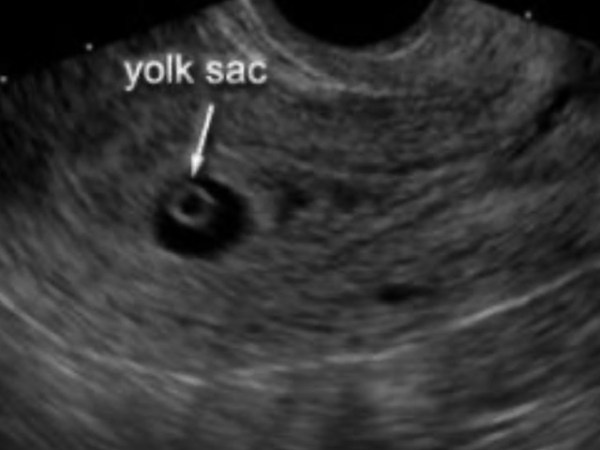

I should start by saying that I haven’t shared any of this with many people (including my family), so if I work with you and you see this, it’s because I trust you and would appreciate confidentiality as I haven’t shared this with my boss either. I internally debated myself about sharing this story and…